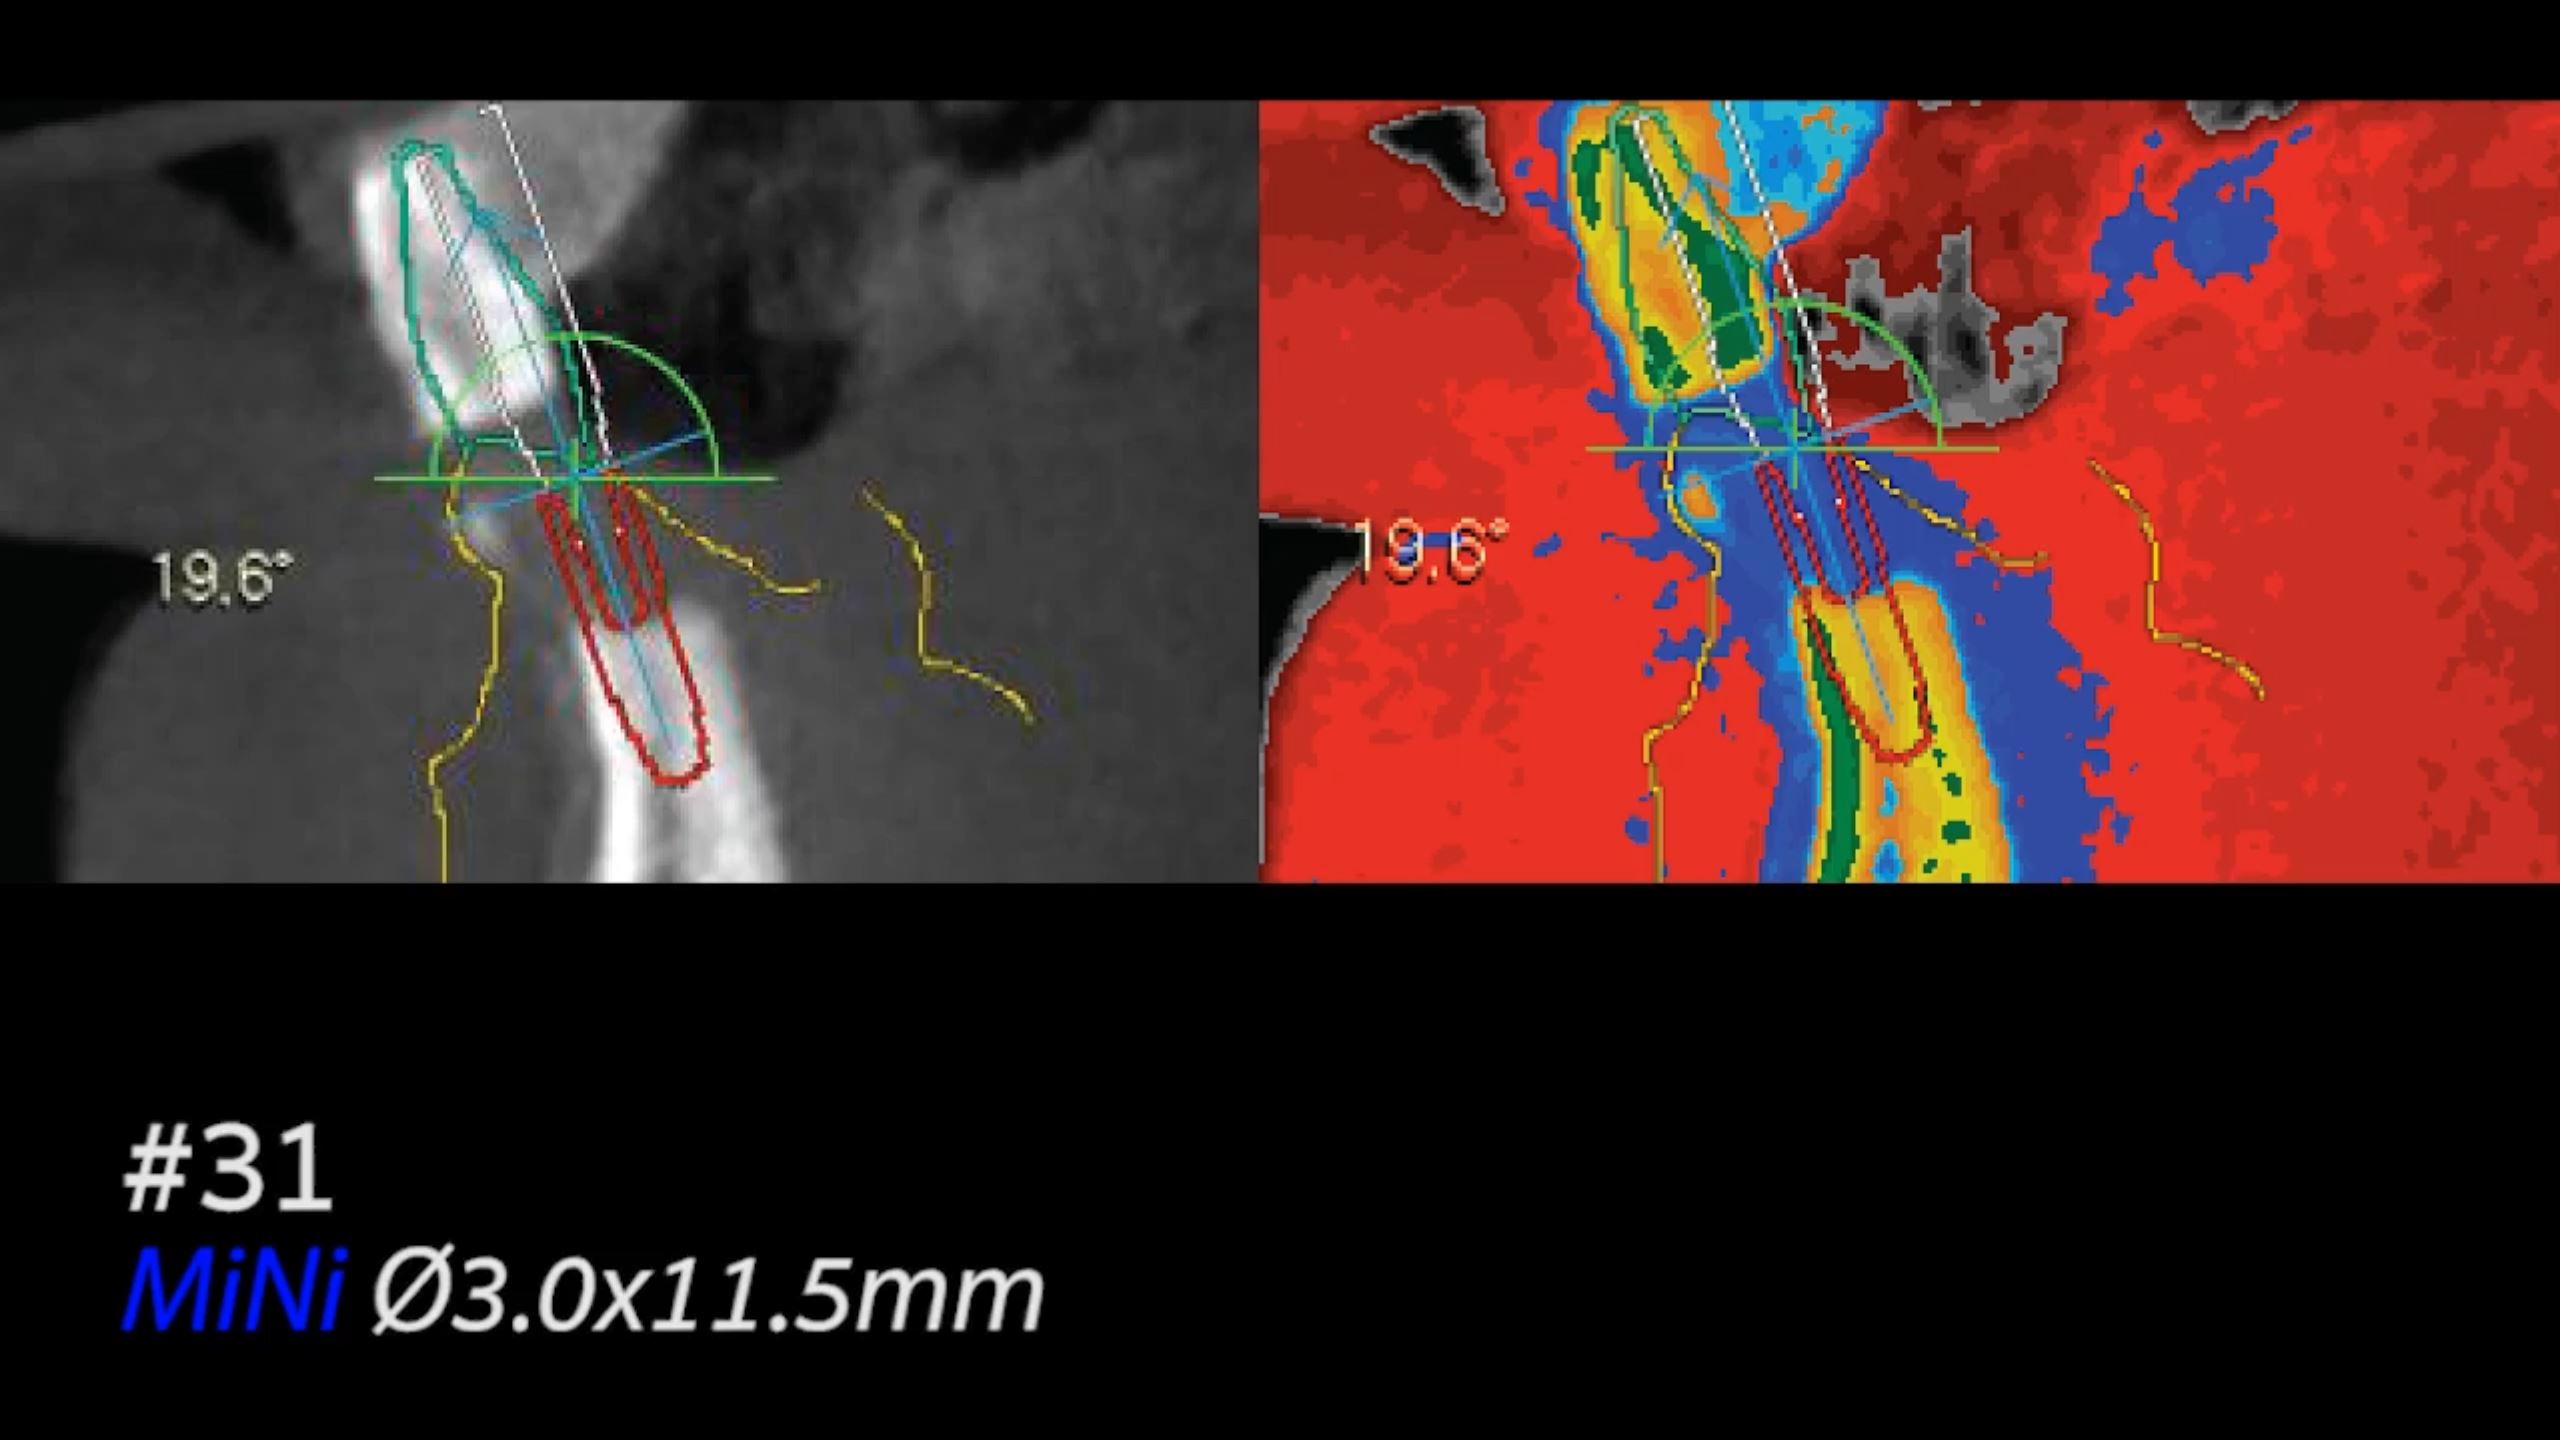

All on six R2GATE Guide Surgery

#11,#13,#16,#21,#23,#26,Digital full mouth prosthetics,Digital Guided Surgery,Edentulous,Flapless,MEG Engine,MEG-TORQ,MEGA ISQ,R2GATE Guide,R2GATE Surgical Kit(AnyRidge),video